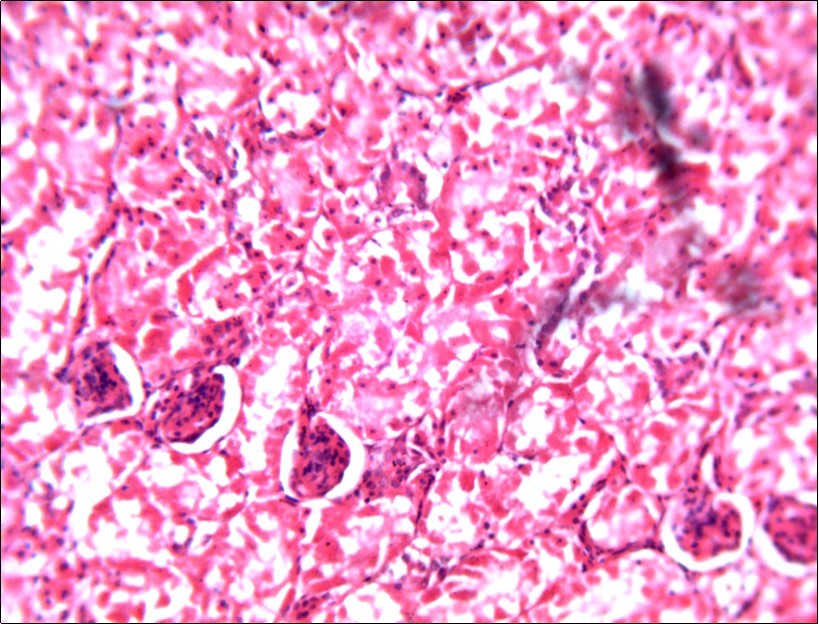

In this study, the reduction in oocyst count observed in the treated group was compared with amprolium could be attributed to the presence of a bioactive compounds azadiractin A which is known to bind membrane cholesterol, altering the integrity of the parasite membrane, resulting in loss of homeostasis and eventual death of the parasite 29]. Also, limonoids contained in NeemAzal® inhibit protein digestion and uptake of vitamins and minerals by the parasites in the gut 17. This action results in impaired nutrient utilization, reduced growth, and multiplication of the parasite which could contribute to the reduced oocyst count observed. Extracts of neem and mahogany when used individually have been reported to reduce oocyst count in avian coccidiosis 11,12. The observed reduction in oocyst count and the significant increase in weight gain of the birds when treated with NeemAzal®, as compared with the negative control group could probably be due to the inhibition of inflammation in the intestinal mucosa which is suggestive of an increased nutrient absorption across the intestinal wall and enhanced feed conversion ratio compared to the negative control this is in agreement with reports by Nwosu et al.12 and Biu et al.11 who also reported an increased weight gain and feed conversion ratio in birds treated with only Khaya senegalensis extracts and Azardiractaindica, respectively. The observed increase in RBC and haemoglobin concentration is indicative of the erythropoieticability of the NeemAzal®, which is beneficial since the Eimeria parasite in the epithelia of the intestines causes bloody diarrhoea and consequently anaemia (Table 1). This finding is in consonance with 15 who reported an anti-anaemic effect of Khaya Senegalensis on phenyl hydrazine-induced anaemia in rats. Neem has been shown to possess anti-anaemic properties in rats 14. The significant increase in mean weight gain in treated birds when compared to the negative control is possibly due to the inhibition of inflammation in the intestinal mucosa which is suggestive of an increased nutrient absorption across the intestinal wall and enhanced feed conversion ratio compared to the negative control. Nwosu et al.12 and Biu et al.11 reported an increased weight gain and feed conversion ratio in birds treated with only Khaya Senegalensis andAzadiractaindica extracts, respectively. In a similar study, Neem acts like toltrazuril exhibiting anticoccidial. In addition, exposure of broiler chickens to 20000 Oocysts of Eimeria tenellacaused generalized degeneration of the caecal glands with massive Oocysts and gametocyts within the caecal glands with fibrosis (Figure 3, Figure 4 & Figure 5), however, broiler chickens treated with NeemAzal® post exposure to 20000 Oocysts of Eimeria tenella, shows equal numbers of caecal tissues with non-observable histopathological lesions (Figure 4), possibly due to the antioxidant and anti-coccidian effects of NeemAzal®. The exact mechanism of action of neem against coccidian parasites is unknown, but a report by the National Research Council 1992 30, suggested that aqueous neem leaf extract, when taken orally, produces an increase in red cells, white blood cells and lymphocyte counts thus enhancing the cellular immune response, increasing antibody production and so most pathogens can be removed before they cause the symptoms associated with disease this was in agreement with this study as seen in Table a remarkable increase of the RBCs.

In addition, the generalized degeneration of the caecal glands, moderate numbers of gametocytes within the glandular regions with fibrosis which underscores reparative process in response to injury evoked by coccidiosis in the chicks which was perhaps brought about by the antioxidant and chemotherapeutic effect of NeemAzal®. The observed increase in RBC and hemoglobin concentration (Table 1) is indicative of the erythropoieticability of NeemAzal®, which is beneficial since the Eimeria parasite in the epithelia of the intestines causes bloody diarrhea and consequently anaemia. This finding is in consonance with 15 who reported an anti-anaemic effect of Khaya senegalensis on phenyl hydrazine-induced anaemia in rats. If the results of this study are juxtaposed with the results of the previous studies on potent antioxidant, hepatoprotective and mitigative role of methanolic extracts of Azadirachtaindica,in both natural and experimental infection with Eimeria species and can be deduced that, NeemAzal® could be said to be a potent antioxidant, chemotherapeutic and tissue protective agent. This study also answered a question on further study advocated to determine the maximum safe levels of neem supplementation because the higher doses, due to its bitterness, may show adverse effects on feed intake which will change the performance parameters of birds (Figure 6 and Figure 7) . Light microscopic inspection of hematoxylin and eosin-stained sections revealed that the epithelial cells of the Cecum were infected by E. tenella(Figure 3 and Figure 4). The results of the safety study showed that exposure of chickens to NeemAzal® at 200mg/kg body weight did not alter the histoarchitecture of liver and kidney (Figure 6 & Figure 7) which is similar to the work conducted in the same environment by a group of Scientists 34. It is therefore recommended that NeemAzal® could be used as a coccidiostat to replace the expensive anti-coccidiostats in the market.

Figure 7.Photomicrograph of kidney of chick administered NeemAzal® at 200 mg/kg showing no observable lesion X250 (H&E).